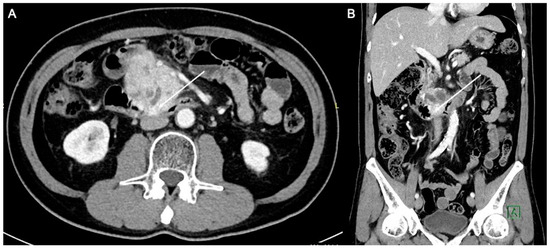

Figure 3.

Axial computed tomography image post open irreversible electroporation. At the location of the tumor invasion of the duodenum, there is a defect in the wall with gas seen (arrow). This likely represents perforation of the duodenum due to breakdown of the ablated tumor.

Figure 4.

Axial (A) and coronal (B) computed tomography images 1 year post open irreversible electroporation. The pancreatic mass now measures approximately 3.9 × 2.6 cm.